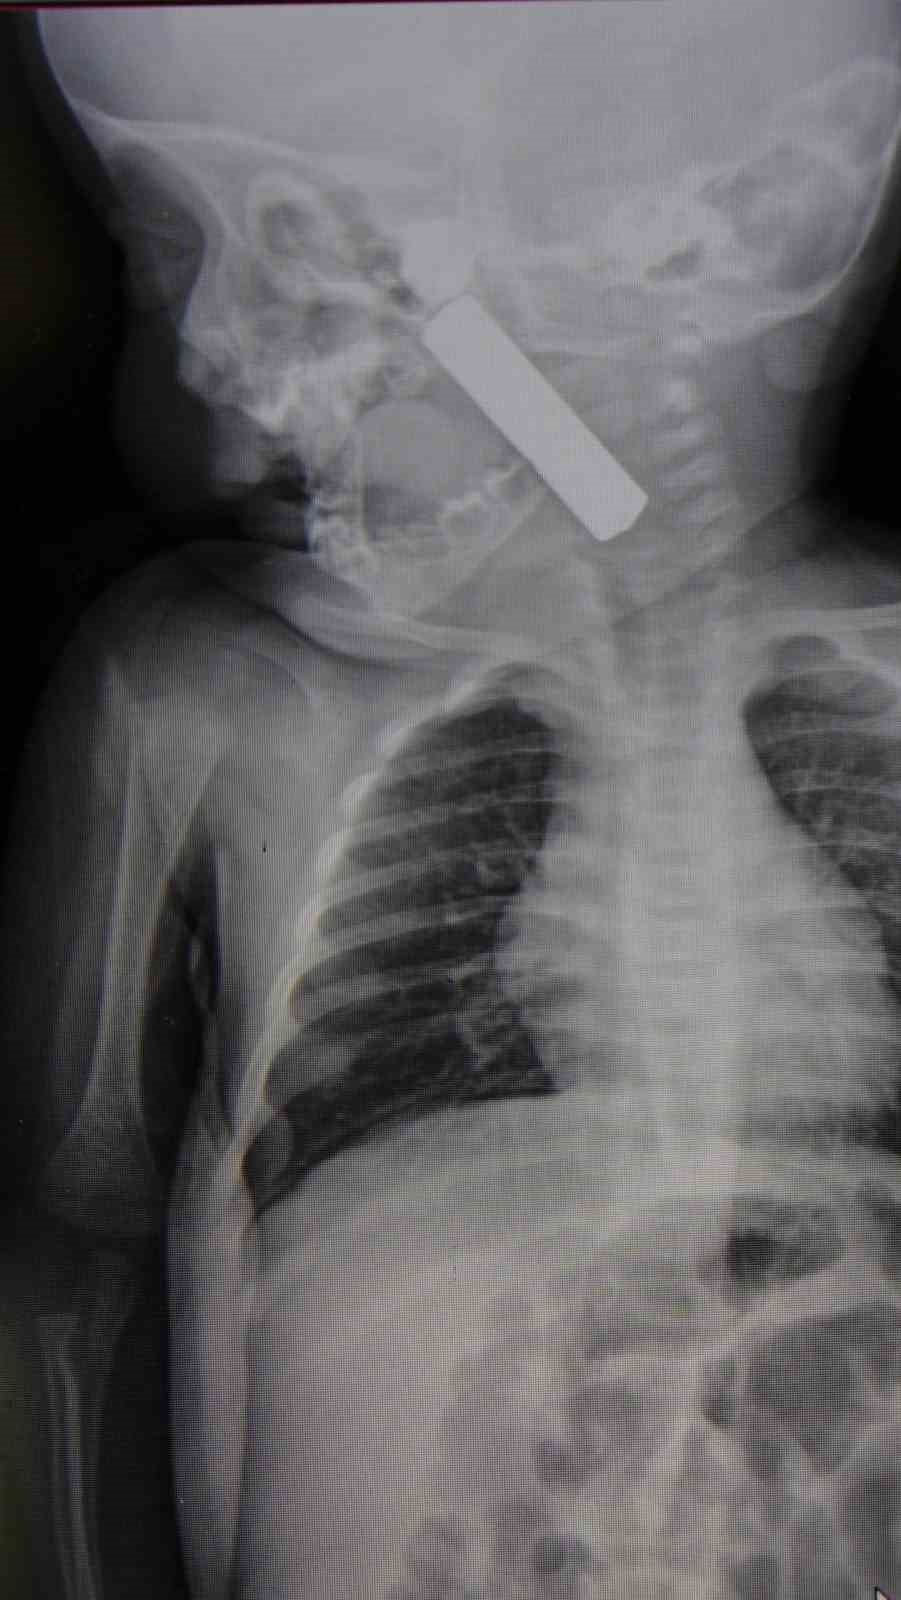

Edinilen bilgiye göre, kusma şikayeti ile ailesi tarafından Karaman Eğitim ve Araştırma Hastanesi acil servisine getirilen 6 aylık E.A. isimli kız bebeğin, yapılan muayene ve tetkiklerde boğazında kumanda pili kaçtığı tespit edildi. Solunum sıkıntısı da yaşayan bebek hemen ameliyata alındı. Çocuk Cerrahisi Uzmanı Doç. Dr. Mehmet Uysal tarafından yapılan ameliyatla bebeğin boğazındaki pil çıkarıldı.

Yaşanan olayla ilgili bilgi veren Doç. Dr. Mehmet Uysal, “Acil polikliniğimize kusma şikayeti ile 6 aylık bir kız bebek getirilmiş ve bize haber verildi. Biz de vakit kaybetmeden geldik, hastamızı gördük. Yapılan tetkikler sonucunda, ağız tabanına oturan ve yemek borusunun birinci darlığına kadar uzanan, kumanda pili dediğimiz bir pille karşılaştık. Filmde ve muayenede bunu gördük. Hastayı ilk gördüğümüzde bayağı siyanotik durumda, solunum sıkıntılıydı ve oksijen satürasyonu 90 civarındaydı. Böyle olunca bir an önce beklemeden hızlı bir şekilde ameliyathaneye götürdük. Orada ameliyathanedeki anestezi uzmanlarımız ve personel bize yardımcı oldu, hasta hızlı bir şekilde entübe edildi. Ondan sonra da laringoskop ve magill forseps dediğimiz malzemelerimizle bu yabancı cismi çıkarmış olduk. Bir an evvel müdahale ettik, iyi ki müdahale ettik, orada ağız tabanında, özellikle ön kısmında hasar oluşmuştu. Müdahale sonrasında da hastanın solunum problemleri bir süre devam etti, bu yüzden 24 saat takip ettik. Herhangi bir problem oluşmayınca 24 saat sonra kontrole gelmek üzere hastayı taburcu ettik” diye konuştu.